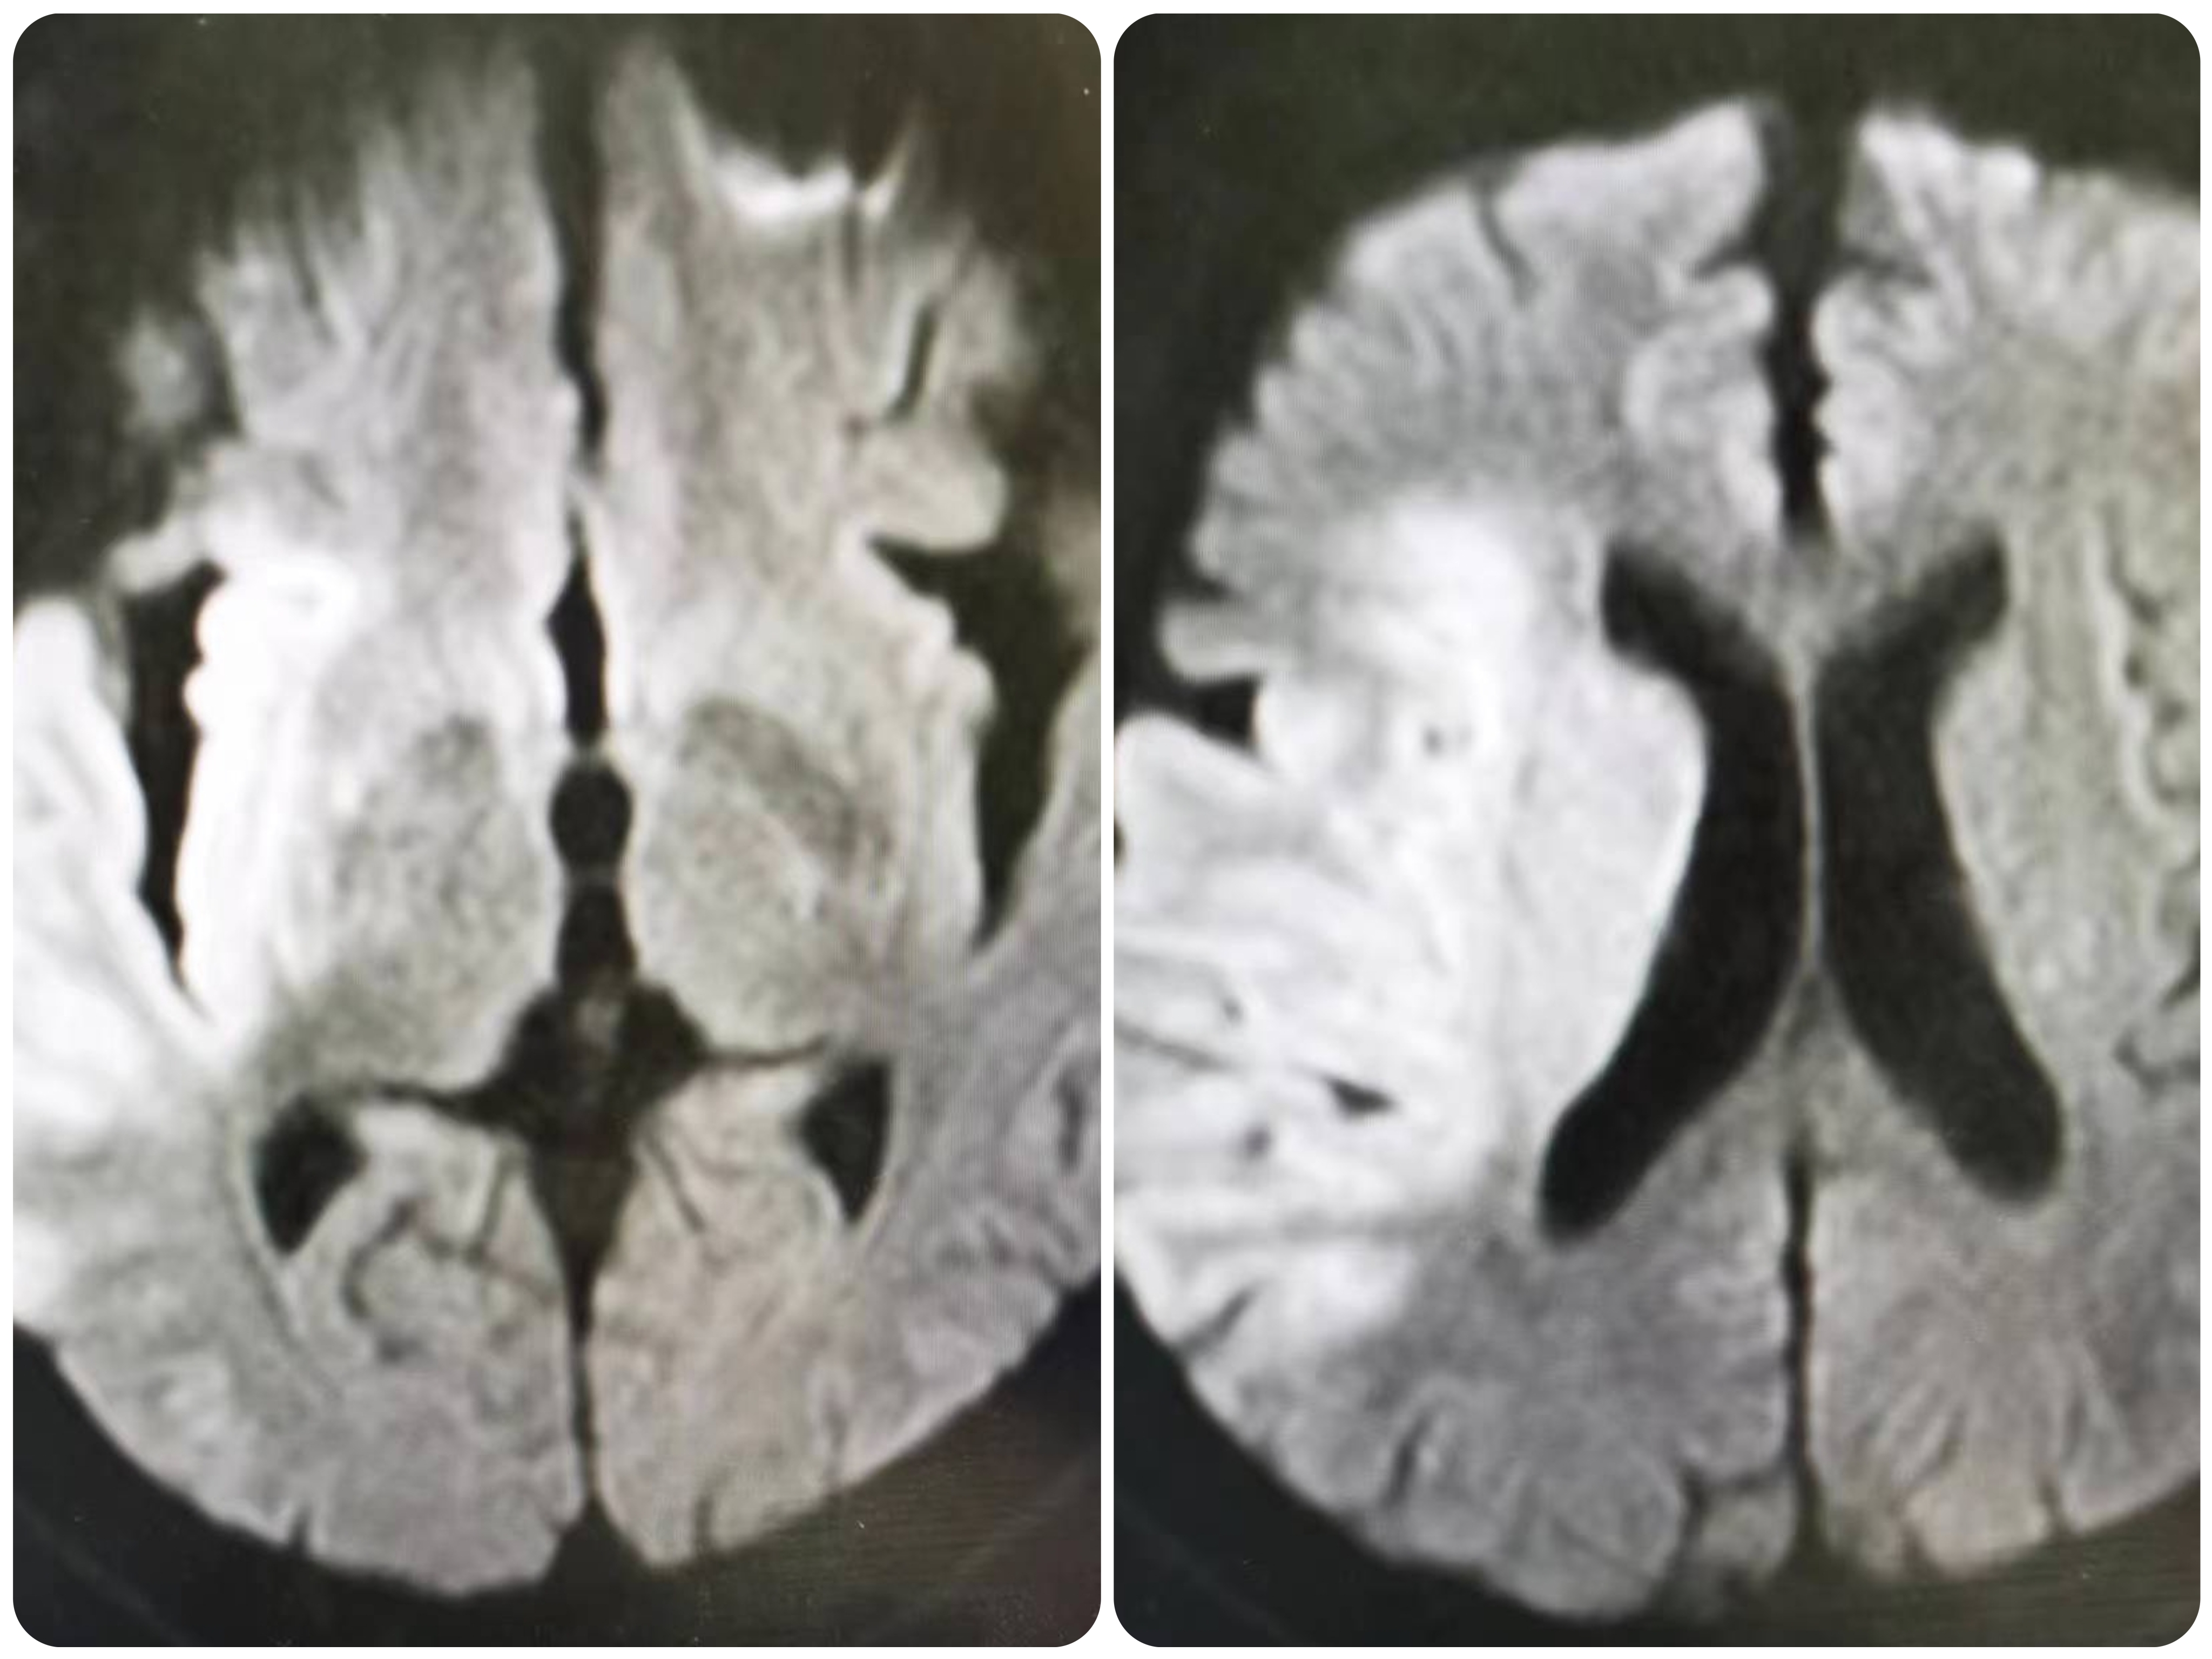

FLAIR序列未见右侧梗死,存在DWI与FLAIR序列不匹配,存在可挽救缺血脑组织,向患者家属详细交代病情及手术风险,家属知情同意后立即桥接血管内治疗。

2、该患DWI显示病灶较大,但FLAIR序列存在不匹配,具备介入治疗指征。